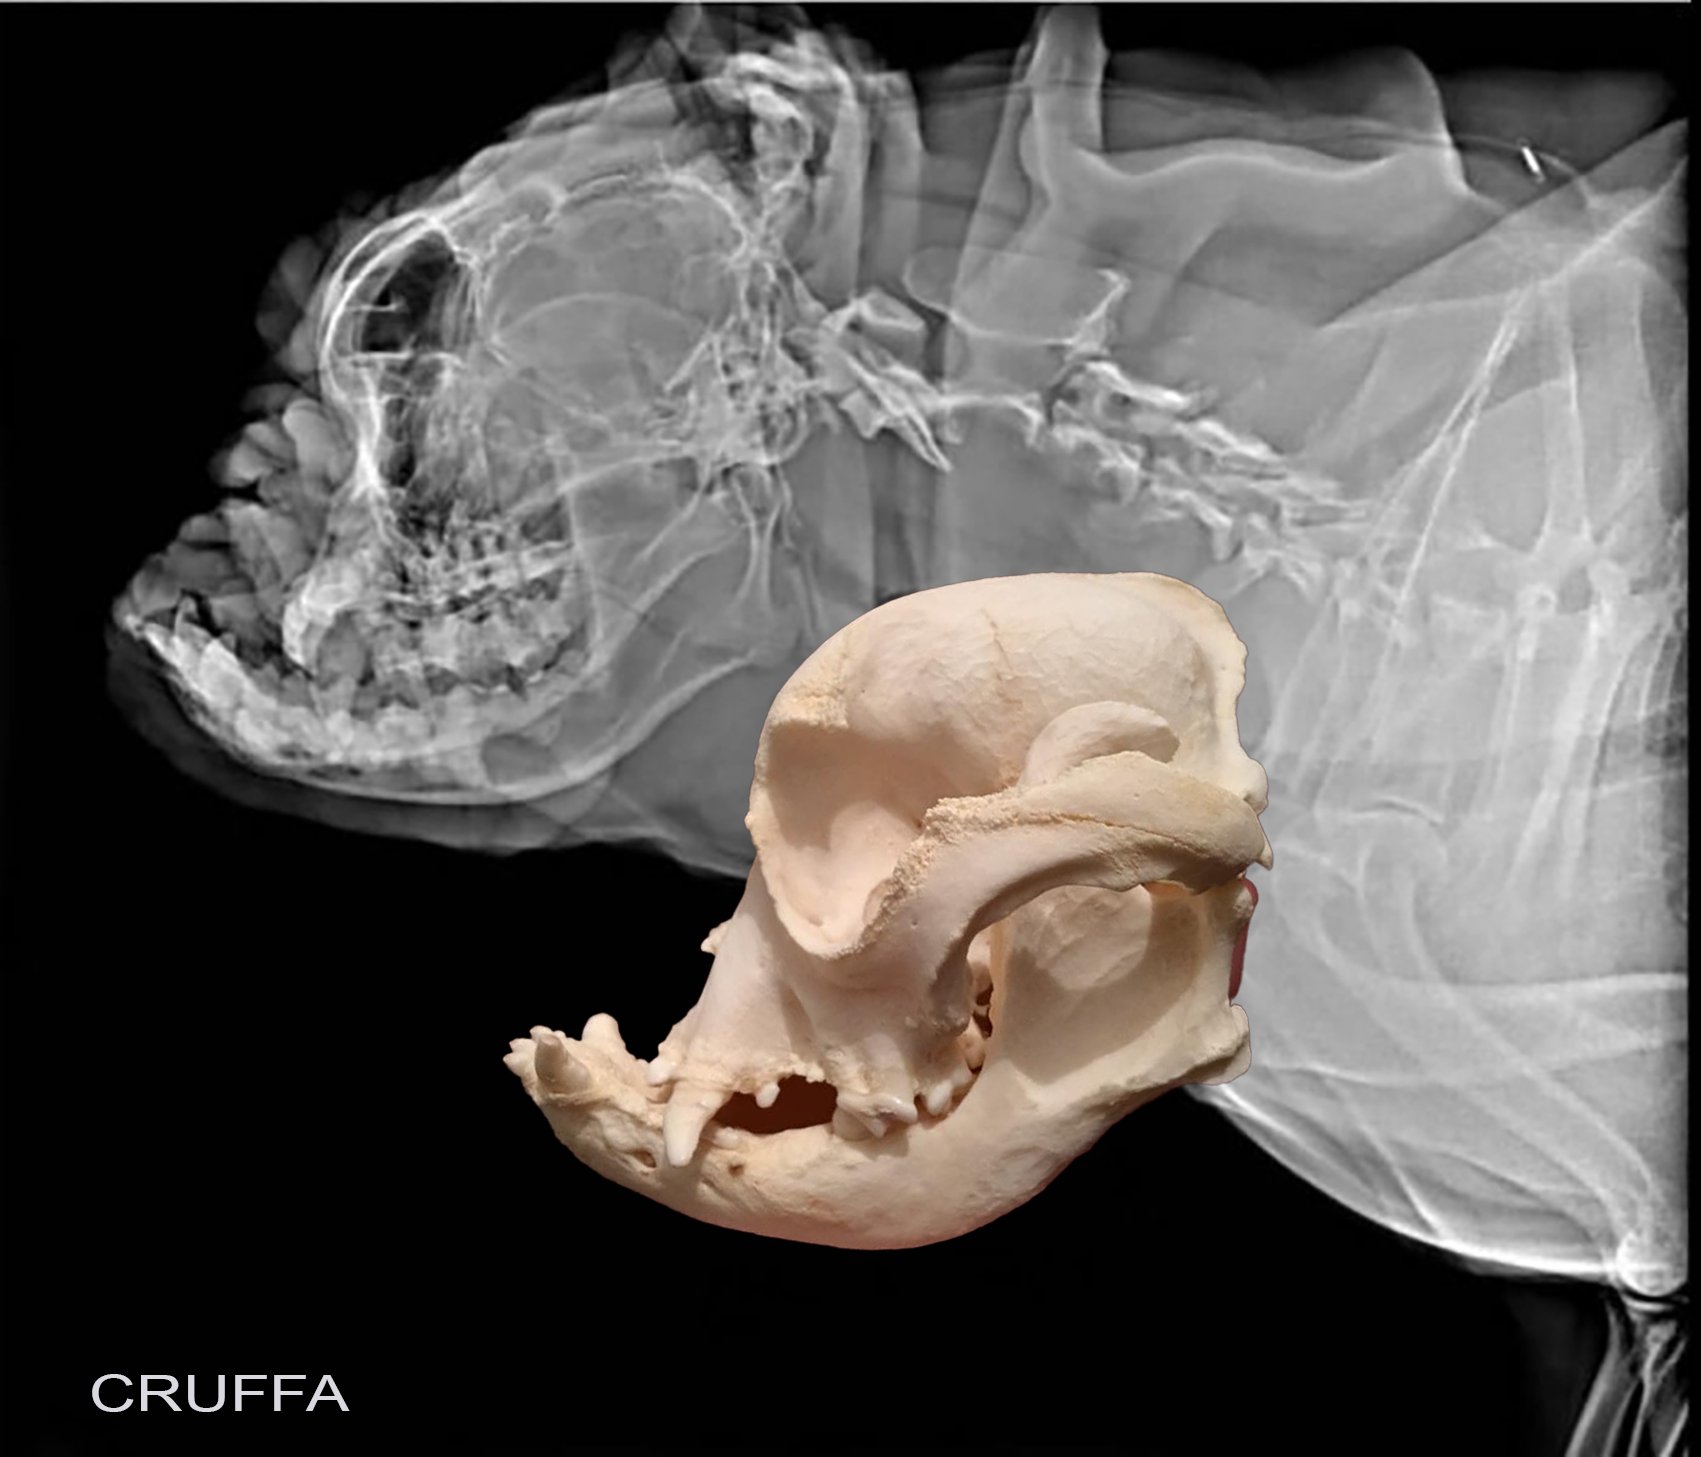

Bulldog skull top

Bulldog skull top, Photo of a french bulldog skull with fangs on Craiyon top

Product Name: Bulldog skull top

English Bulldog Skull Bone Clones Inc. Osteological Reproductions top, Replica English Bulldog Skull Male Skulls Unlimited top, English Bulldog Skull rescuecritters top, Dog Skull Stylized Skeleton French Bulldog Stock Illustration top, Domestic English Bulldog Skull Replica top, English Bulldog Skull Animal skeletons Painted animal skulls top, Real Dog Specimen Bulldog Skull Model Dog Skull Taxidermy Supplies top, American bulldog Skull Base top, French Bulldog Skull top, Photo of a french bulldog skull with fangs on Craiyon top, Jemima Harrison on X top, French bulldog skull top, English Bulldog Skull 3D model by MCMI MCMI 310dfea top, Canine dog skull skeleton French bulldog dog with brachycephalic top, English bulldog skull top, Bulldog Skull by Alex Surcica top, English Bulldog Skull Vs. Wolf Skull r pics top, Bulldog Skull High Resolution STL Scan for Animal Reproduction top, English Bulldog Skull Female Teaching Quality Replica top, English Bulldog Skull by CabinetCuriosities on DeviantArt top, Airedale Skull Bone Clones Inc. Osteological Reproductions top, Photo of a french bulldog skull on Craiyon top, File Bulldog skull.JPG Wikipedia top, French Bulldog Pup r skulls top, English Bulldog Skull Art Print top, Bulldog English bulldog Dog skull top, French Bulldog Skull Unique Structure Of Cute French Bulldog top, Front and side view of a french bulldog Canis lupus familiaris top, English Bulldog Skull by Z a r g o s on DeviantArt top, Brachycephalic DogThe Veterinary Expert Pet Health top, French Bulldog Skull 01 3D Model TurboSquid 1535532 top, 1pcs natural fossil French bulldog skull quartz crystal carved reiki gem 2 top, English Bulldog Skull more Skulls Bones and Oddities Amino top, Chris Haas Art Progress on the French Bulldog skull. art top, British Bulldog Skull Replica 3D Printed Vegan Taxidermy Cruelty top, 1pc Natural Fossil French bulldog Skull Quartz Crystal Carved Figurines Gem 2 top, Bulldog skull by bigredsharks Skull art Skull Rabbit anatomy top, English bulldog skull. r Damnthatsinteresting top, Photo of a french bulldog skull with fangs on Craiyon top, Scientists prove that Romans were breeding small bulldogs top, English Bulldog skull change in less than 100 years Flickr top, English bull dog skull DRAWING. Behance top, English bulldog skull Kids T Shirt top, Real Domestic Dog Skull English Bulldog Skulls Unlimited top, Skull of a bulldog c2 by Historic illustrations top, American bulldog Skull Base top, 1pc Natural chalcopyrite French bulldog Skull Quartz Crystal Skull Figurines 2 top, Bulldog Skull Etsy Canada top, File Skull of bulldog Keulemans.png Wikipedia top, 3 4 view photo of a french bulldog skull on Craiyon top.

English Bulldog Skull Bone Clones Inc. Osteological Reproductions top, Replica English Bulldog Skull Male Skulls Unlimited top, English Bulldog Skull rescuecritters top, Dog Skull Stylized Skeleton French Bulldog Stock Illustration top, Domestic English Bulldog Skull Replica top, English Bulldog Skull Animal skeletons Painted animal skulls top, Real Dog Specimen Bulldog Skull Model Dog Skull Taxidermy Supplies top, American bulldog Skull Base top, French Bulldog Skull top, Photo of a french bulldog skull with fangs on Craiyon top, Jemima Harrison on X top, French bulldog skull top, English Bulldog Skull 3D model by MCMI MCMI 310dfea top, Canine dog skull skeleton French bulldog dog with brachycephalic top, English bulldog skull top, Bulldog Skull by Alex Surcica top, English Bulldog Skull Vs. Wolf Skull r pics top, Bulldog Skull High Resolution STL Scan for Animal Reproduction top, English Bulldog Skull Female Teaching Quality Replica top, English Bulldog Skull by CabinetCuriosities on DeviantArt top, Airedale Skull Bone Clones Inc. Osteological Reproductions top, Photo of a french bulldog skull on Craiyon top, File Bulldog skull.JPG Wikipedia top, French Bulldog Pup r skulls top, English Bulldog Skull Art Print top, Bulldog English bulldog Dog skull top, French Bulldog Skull Unique Structure Of Cute French Bulldog top, Front and side view of a french bulldog Canis lupus familiaris top, English Bulldog Skull by Z a r g o s on DeviantArt top, Brachycephalic DogThe Veterinary Expert Pet Health top, French Bulldog Skull 01 3D Model TurboSquid 1535532 top, 1pcs natural fossil French bulldog skull quartz crystal carved reiki gem 2 top, English Bulldog Skull more Skulls Bones and Oddities Amino top, Chris Haas Art Progress on the French Bulldog skull. art top, British Bulldog Skull Replica 3D Printed Vegan Taxidermy Cruelty top, 1pc Natural Fossil French bulldog Skull Quartz Crystal Carved Figurines Gem 2 top, Bulldog skull by bigredsharks Skull art Skull Rabbit anatomy top, English bulldog skull. r Damnthatsinteresting top, Photo of a french bulldog skull with fangs on Craiyon top, Scientists prove that Romans were breeding small bulldogs top, English Bulldog skull change in less than 100 years Flickr top, English bull dog skull DRAWING. Behance top, English bulldog skull Kids T Shirt top, Real Domestic Dog Skull English Bulldog Skulls Unlimited top, Skull of a bulldog c2 by Historic illustrations top, American bulldog Skull Base top, 1pc Natural chalcopyrite French bulldog Skull Quartz Crystal Skull Figurines 2 top, Bulldog Skull Etsy Canada top, File Skull of bulldog Keulemans.png Wikipedia top, 3 4 view photo of a french bulldog skull on Craiyon top.